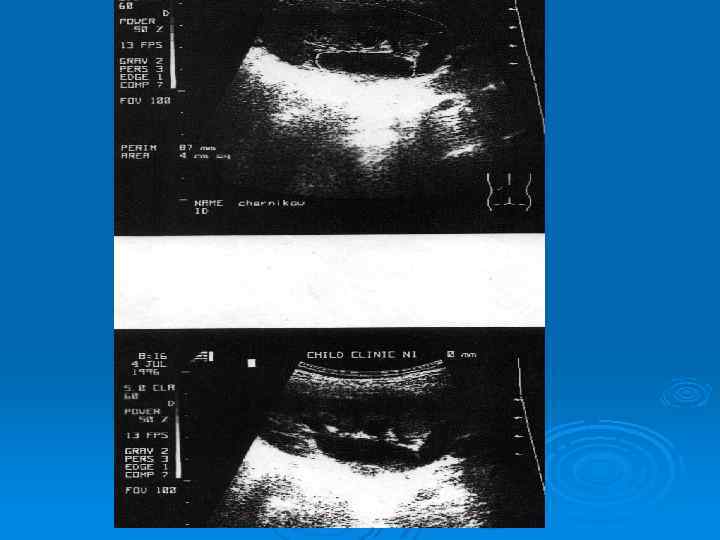

Утолщение стенки лоханки при остром пиелонефрите

Абсцесс верхнего полюса почки у ребенка, 11 лет